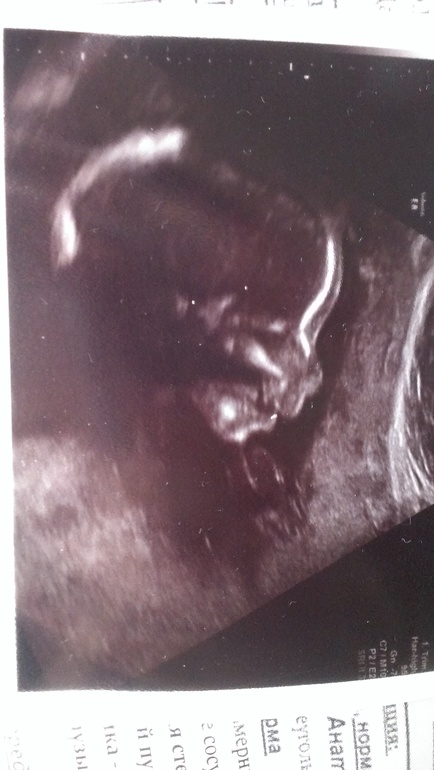

Наш второй узи-скрининг))))

УЗИ, КТГ, доплерНаконецто дождались мы 22недельки)))ходили вместе со средней дочкой)))она видела братика на втором экране)) серьёзно так рассматривала))))он заметно подрос с 18недельки)уже весь не помещается на экране))))нам в третий раз подтвердили сыночка )чему я очень рада))))всё у него хорошо ,соответствует всё нормам)

сделали нам фоточку на память)головка только поместилась))))в общем рада очень)что всё хорошо ,а то всё время переживала)))теперь увижу своего зайчика только летом на 32недеде)на узи....